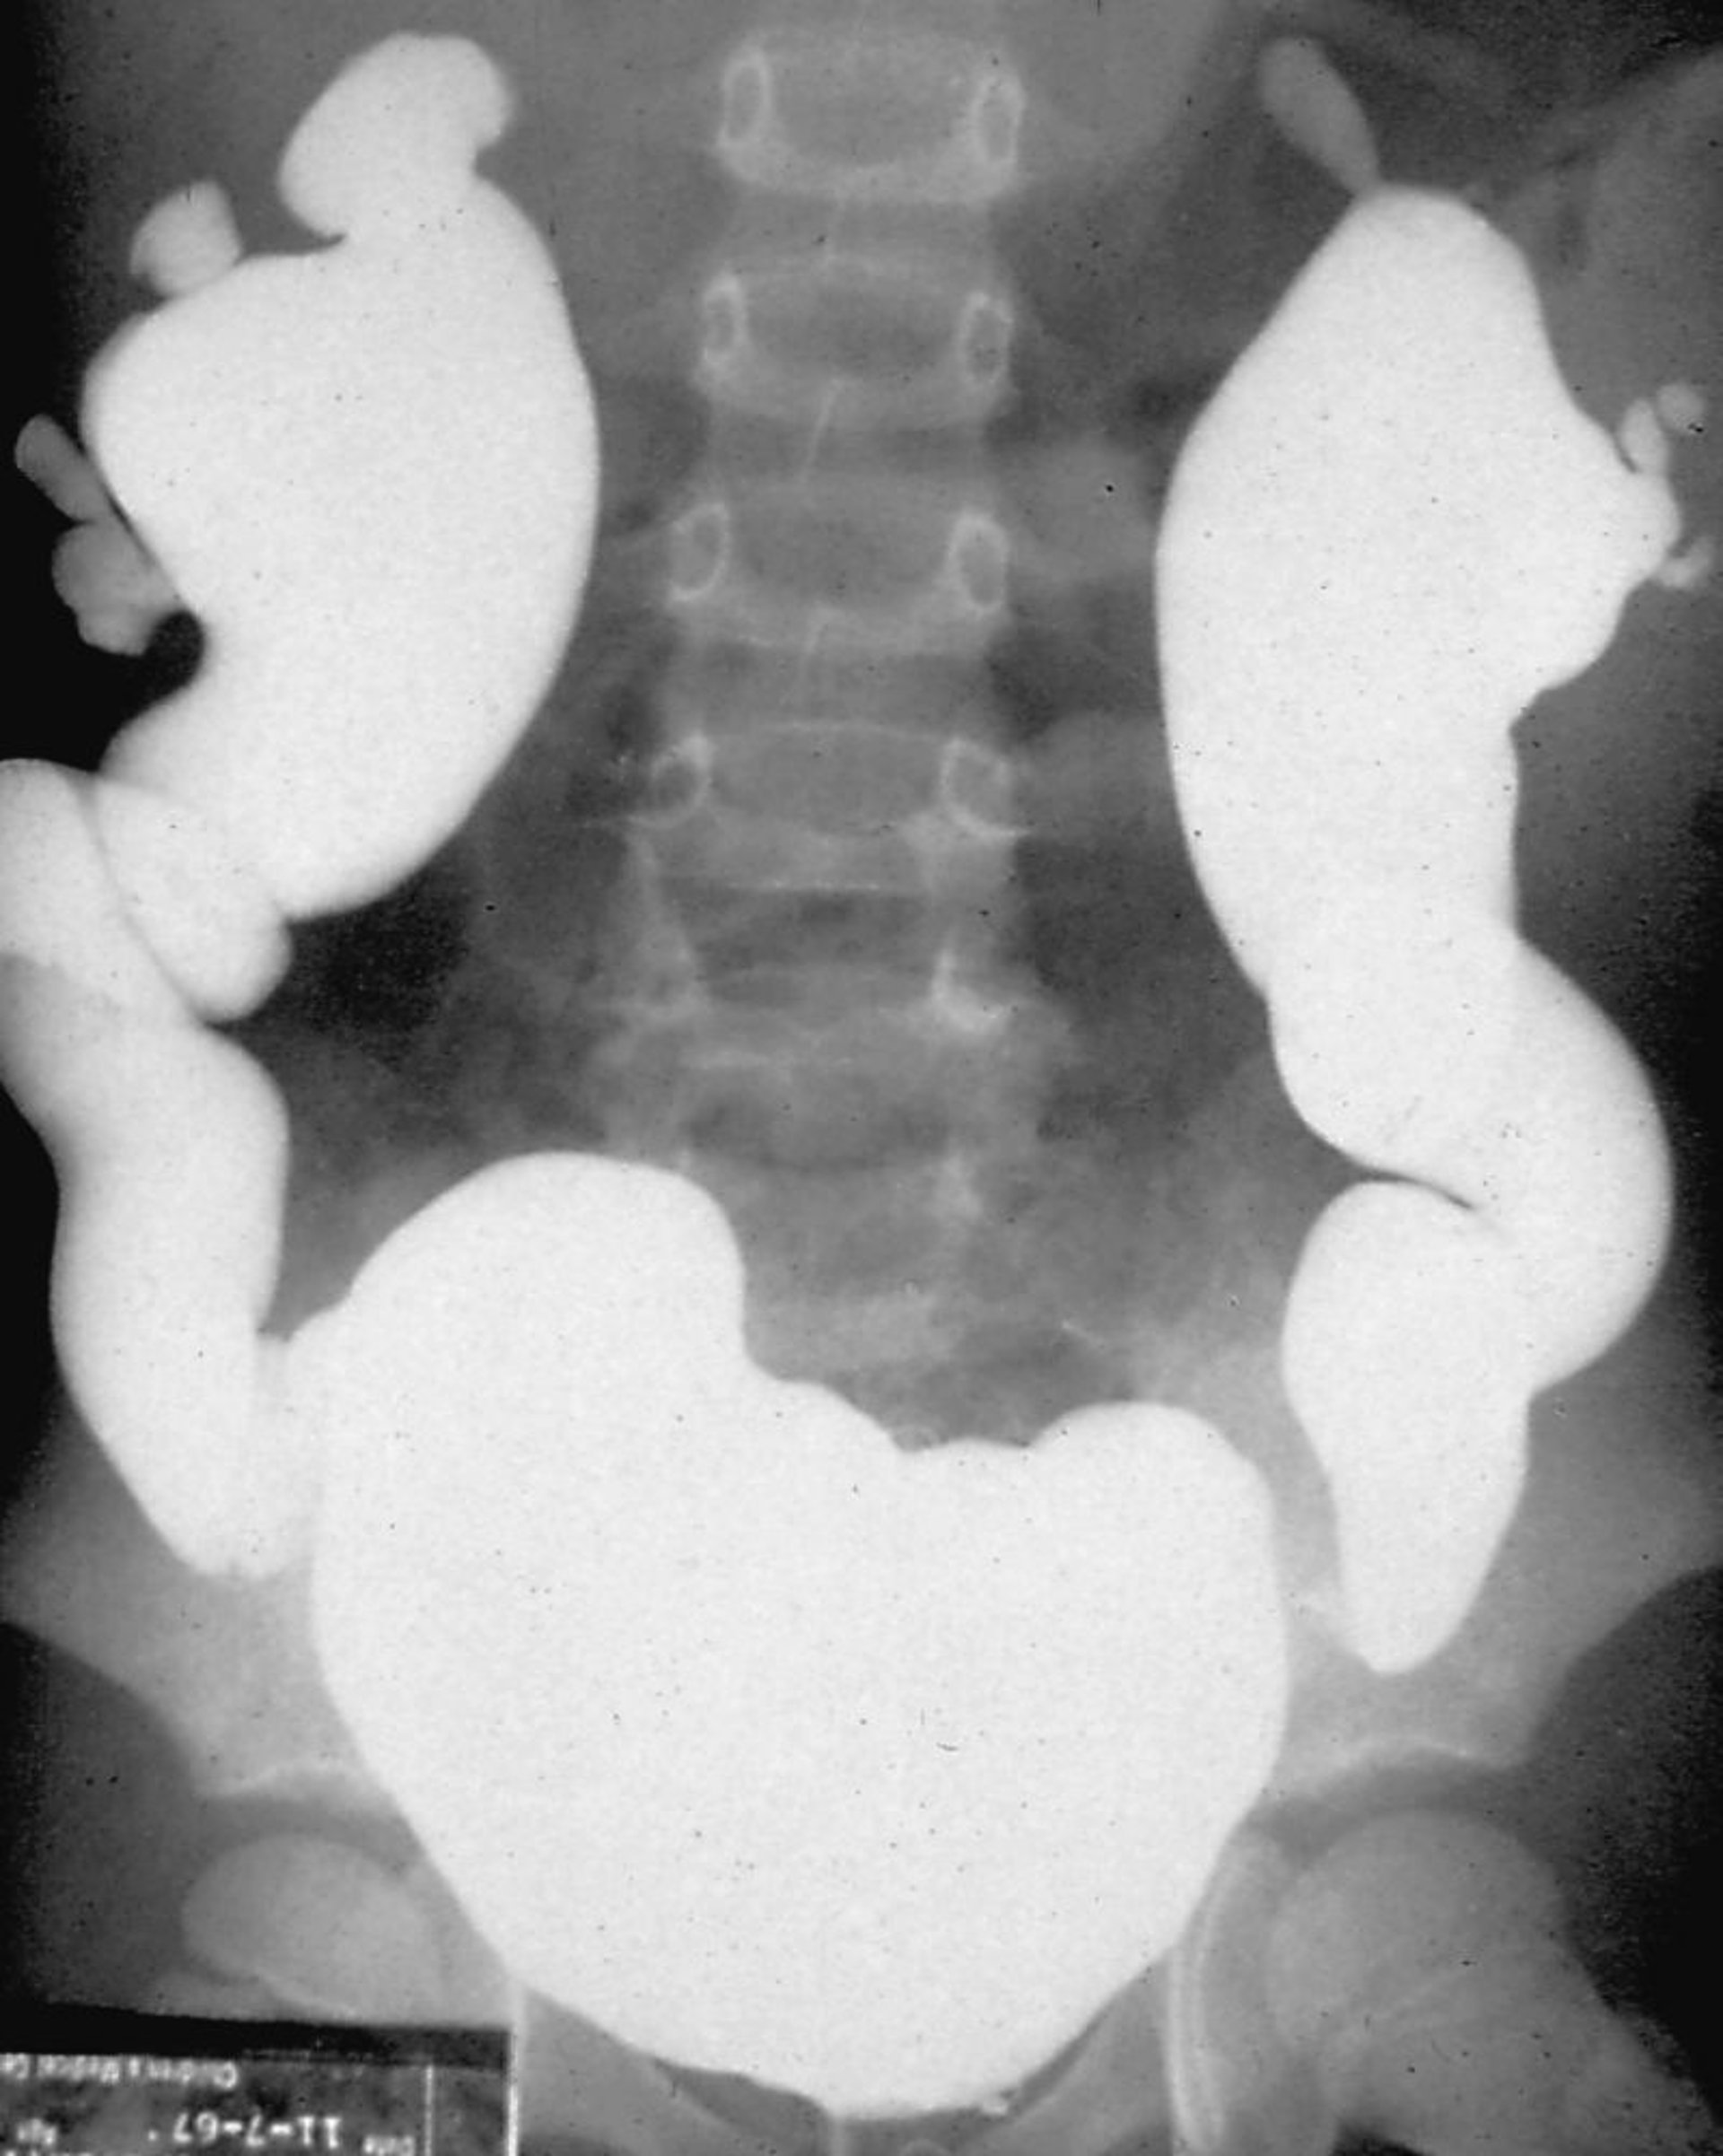

Néphropathie de reflux (urétrocystogramme mictionnel)

L'urétrocystographie mictionnelle est effectuée en remplissant la vessie avec un produit de contraste et en observant le reflux sous radioscopie, soit pendant la phase de remplissage de la vessie, soit pendant la miction.